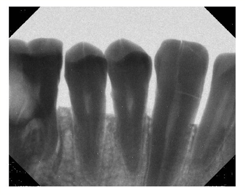

Dental imaging today is quite common, in fact most dentist will take an image at least once a year. The patients typical either sit in dental chair as can been seen in the image below to the left. The dentist then places a piece of film as seen in the image below in the middle in the patient’s mouth and takes X-ray images. After some processing the dentist looks at images as seen in the image to the right. The dentists will typically blow-up these images so they can examine cavities, fillings, gum line, roots and etc. very closely.

Dental Image